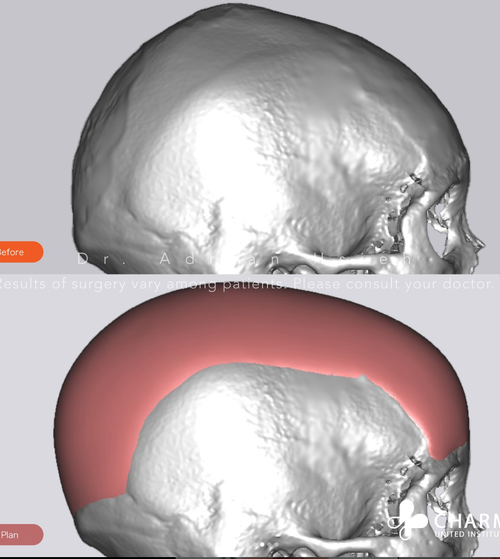

this girl went from brachy to meso. now her hardmaxx ceiling is higher. this seems cheap in taiwan, will you get this thecel?? I need this for the advancements I have in mindPitch, Yaw, and Roll

View attachment 4063720